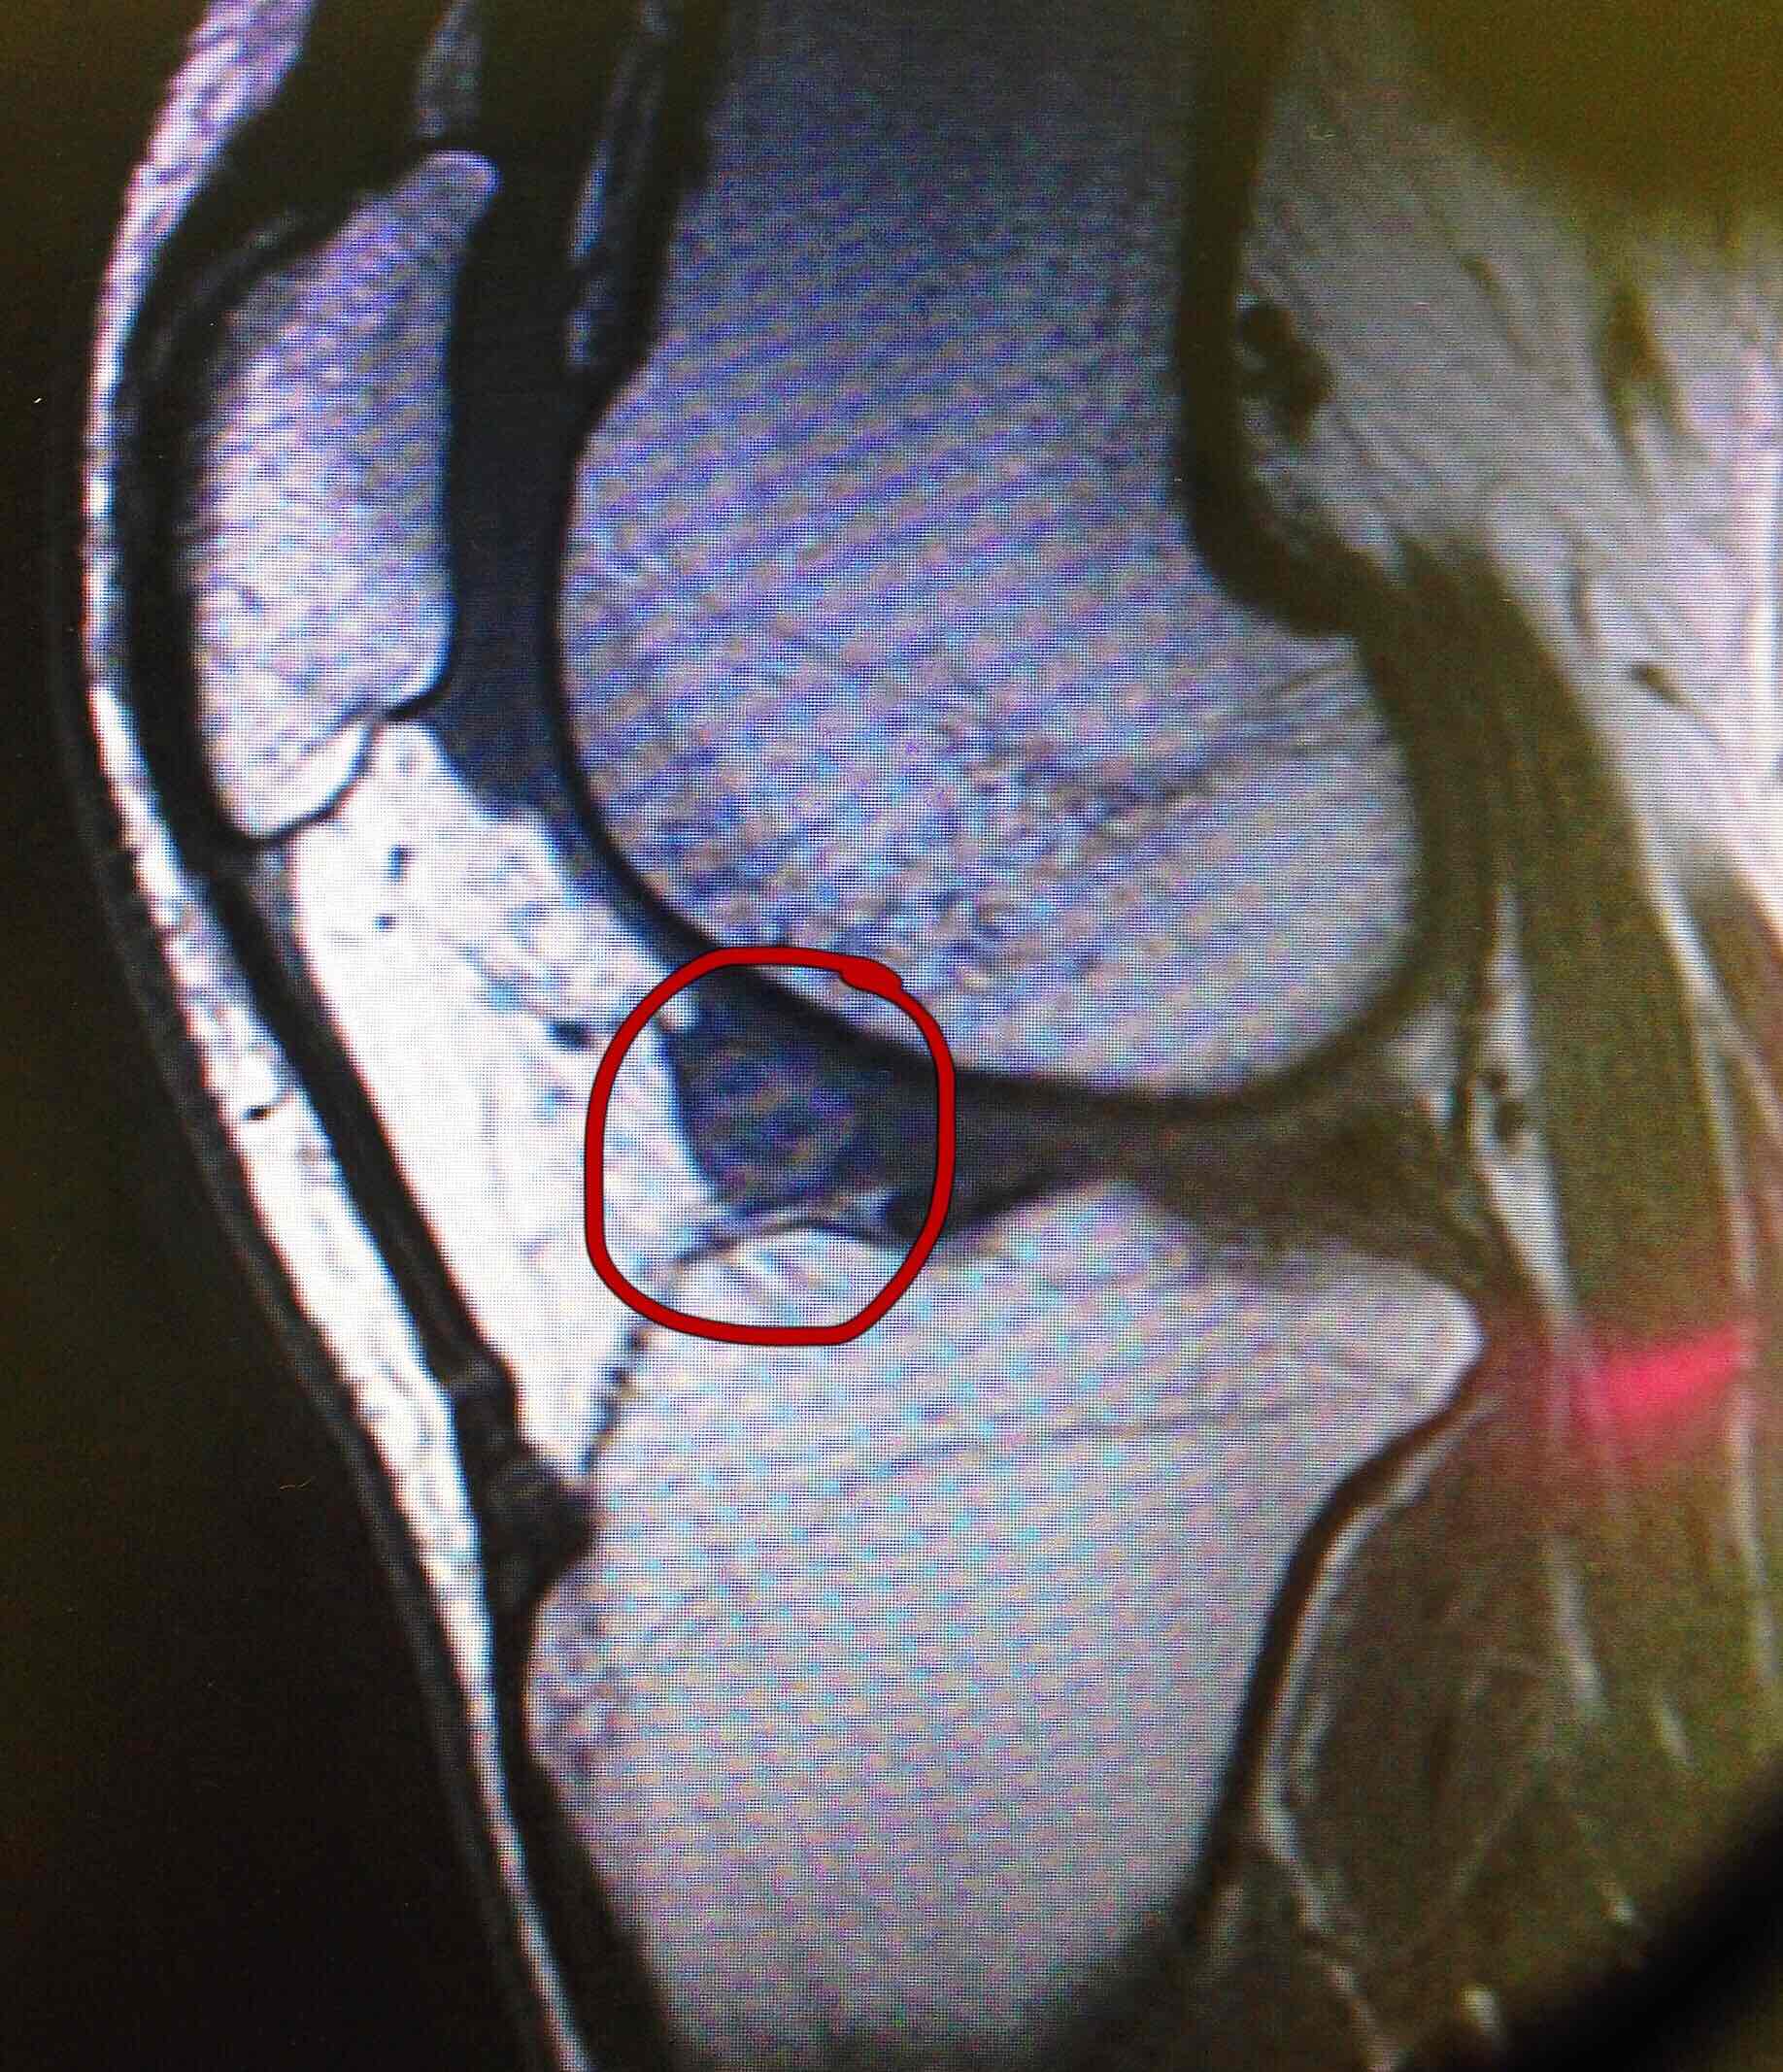

膝关节交锁怎么回事要手术吗为什么有时手术效果不好还复发

交锁这个词在医学上往往代表着关节处于一种锁定的状态,也就是说正常

引起膝关节卡顿的原因有很多,常见原因是半月板撕裂和关节内游离体.